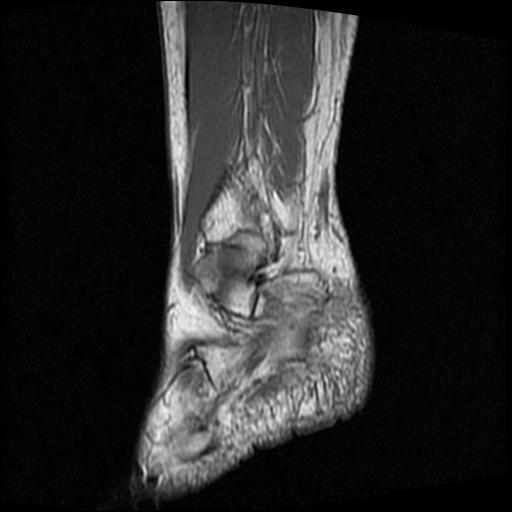

女性,70岁,右侧跟骨疼痛2个月,负重时加剧,不负重时不疼。

跟骨慢性炎症.伴脓肿形成.

考虑  跟骨骨髓炎

跟骨长t1长t2信号异常,边缘模糊(肿瘤一般边界清楚,故肿瘤不考虑),压脂像呈高信号--骨髓水肿(炎症?)。